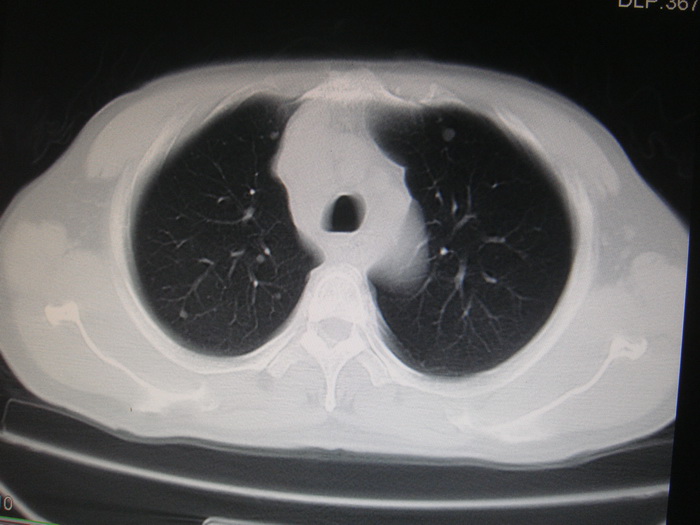

标题: CT28366:男性,45岁,偶尔发现右颈部肿块行胸部CT扫描。 [打印本页]

男性,45岁,偶尔发现右颈部肿块行胸部ct扫描。

两肺多发结节灶及纵膈淋巴结肿大考虑为转移

两肺多发性转移瘤,纵隔淋巴结转移。

两肺多发性转移瘤,纵隔淋巴结转移。食道中上段管壁似乎增厚,作相关检查。